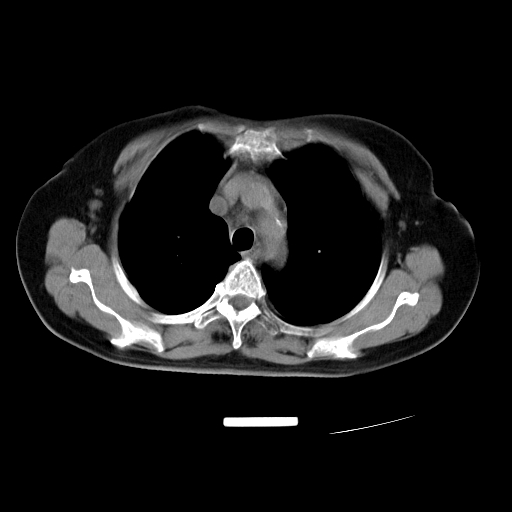

以下是引用zjzjr在2007-3-23 13:28:00的发言:[br]右肺上叶后段可见一结节状高密度影,可见毛刺征,胸膜凹陷征及血管导入征,纵隔内可见肿大淋巴结影.考虑右肺上叶周围型肺癌伴纵隔淋巴结转移.

以下是引用zjzjr在2007-3-23 13:28:00的发言:[br]右肺上叶后段可见一结节状高密度影,可见毛刺征,胸膜凹陷征及血管导入征,气管前腔静脉后可见肿大淋巴结影.考虑右肺上叶周围型肺癌伴纵隔淋巴结转移.